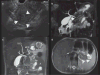

Results: We identified 48 AIP cases: 30 from literature review, 14 from INSPPIRE, and 4 from CUSL. The median age at diagnosis was 13 years (range 2-17 years). Abdominal pain (43/47, 91%) and/or obstructive jaundice (20/47, 42%) were the most common symptoms at diagnosis. Elevated serum IgG4 levels were only observed in 9/40 (22%) children. Cross-sectional imaging studies were abnormal in all children including hypointense global or focal gland enlargement (39/47, 83%), main pancreatic duct irregularity (30/47, 64%), and common bile duct stricture (26/47, 55%). A combination of lymphoplasmacytic inflammation, pancreatic fibrosis, and ductal granulocyte infiltration were the main histological findings (18/25, 72%). Children with AIP had a prompt clinical response to steroids. Complications of AIP included failure of exocrine (4/25, 16%) and endocrine (3/27, 11%) pancreas function.